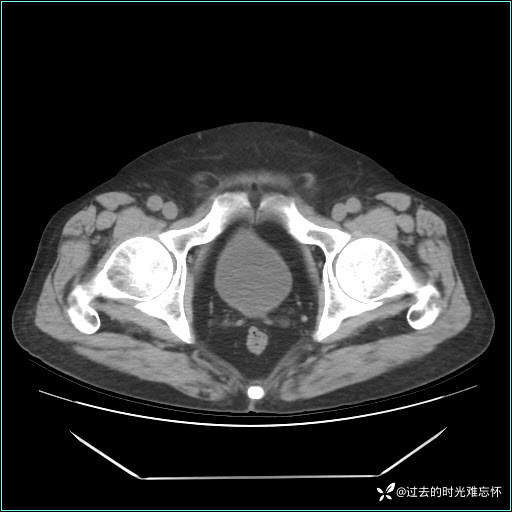

男子肚子大如孕晚期,一看腹腔竟被脂肪填满了...

患者男,71 岁,因「反复腹痛腹胀 1 月」入院。

现病史:患者 1 月前无明显诱因下出现腹痛腹胀症状,腹痛呈隐痛,当时未予以重视,后症状有所加重,常在进食辛辣刺激油腻等食物后出现腹痛,口服药物治疗症状能得到控制,病情控制一般。现为求诊治来我院,拟“腹痛”入院。病程中患者神志清楚,精神一般,无咳嗽咳痰,无恶心呕吐,近期体重无明显变化。